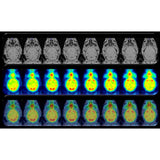

Combining PET with MRI enhances the capabilities to study detailed morphological changes in different organs and tumours, adding more precise information of the distribution and behaviour of the PET tracer.

Bruker’s sequential PET/MR instruments are offered at 3T for translational research and at 7T and 9.4T for high-field applications in mice and rats using Bruker’s BioSpec Maxwell MRI technology. This is combined with Bruker’s SiPM PET technology, providing the highest sensitivity, high spatial resolution and precise quantification across the entire FOV. A touch screen controlled motorized animal transport system simplifies the workflow and supports a broad spectrum of application fields, such as oncology, functional and anatomical neuroimaging, cardiac imaging and stroke models. All of this powered by the Paravision 360 software, allowing MRI users to follow familiar MR imaging workflows to obtain valuable PET/MR data immediately.

- Streamlined workflows including automatic image stitching, MR based attenuation correction and PET/MR image fusion